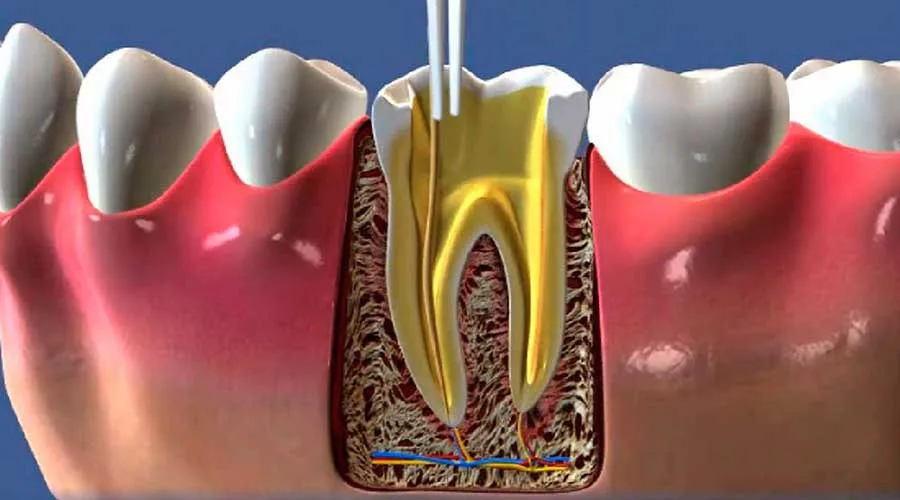

Optar por uma clínica com especialista em endodontia é uma decisão estratégica para quem busca tratamentos dentários eficazes. A endodontia é a área da odontologia focada no cuidado da polpa dentária e das estruturas internas dos dentes.

Uma clínica com especialista em endodontia oferece intervenções que são pautadas pela precisão técnica. Isso se deve à formação específica e ao conhecimento aprofundado do profissional sobre a anatomia das raízes:

Remoção completa da polpa infectada ou inflamada;

Limpeza e desinfecção profunda dos canais radiculares;

Uso de materiais biocompatíveis para uma obturação estável.

Essas etapas são fundamentais para eliminar focos bacterianos que podem atingir o osso alveolar. O rigor técnico em cada detalhe do processo evita recidivas e protege a integridade do elemento dental tratado.

A preservação do dente natural é o maior benefício da endodontia, evitando a necessidade de extrações e próteses. Manter a raiz original protege a função mastigatória e a harmonia estética da fisionomia.

Ferramentas como localizadores apicais e sistemas rotatórios aumentam a eficiência da limpeza interna dos canais. A tecnologia aliada ao conhecimento técnico resulta em uma recuperação ágil e com menores chances de intercorrências.